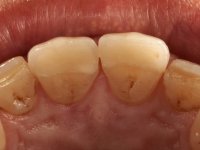

Male patient, 64 years old, non-smoker. Presented widespread dental wear. Both superior and inferior central incisives were lacking enamel on incisal edges, with exposed dentin. Superior central incisives had been previously restored with composite resin, which offered tolerable aesthetics and was prone to frequent fracturing.

Frequent fracturing of composite resin restorations, in central upper incisives. Patient was also displeased with the “aged” look of his teeth.